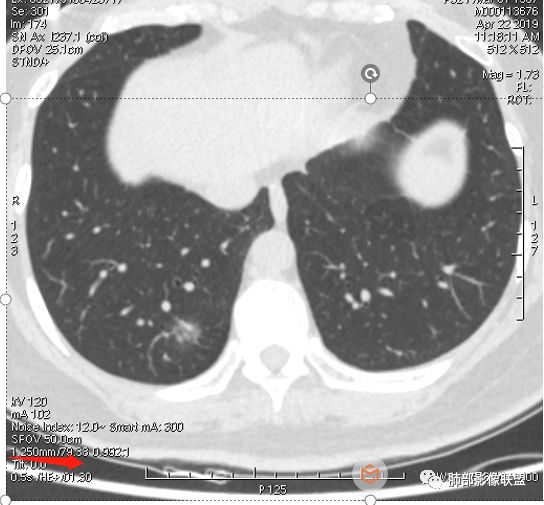

晨读:52f,体检发现右下肺结节,空洞、周围晕征(磨玻璃),局部血管影增粗,考虑1.真菌感染;2.GPA或不典型单发转移待排。

体检发现肺部结节,右下肺混合密度结节,结节中心空泡,壁光滑,结节边缘模糊,血管在结节内增粗,矢状位前基底段还有一片磨玻璃影,所以考虑良性结节可能,炎性肉芽肿?抗炎后复查。腺癌合并炎性改变待排。

晨读:中老年女性,体检来诊。右肺下叶后基底段近胸膜下mGGN,其内实性成分似见毛刺及分叶,并见空泡征,周围GGO边界清楚,近肺门端见血管影伸入病灶并略显扩张,病变与支气管关系观察欠佳。多考虑恶性,腺癌可能性大。鉴于首次检查,常规建议抗炎治疗后复查,观察病灶变化情况,再决定下一步诊疗方向。

患者后来到上海做了手术,电话回访告知结果为粘液腺癌